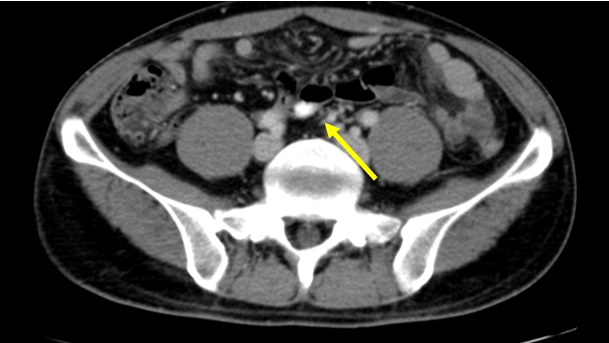

【画像所見まとめ】

• 脾多発腫瘤、脾門部多発リンパ節腫大

• 腸管内に錠剤あり